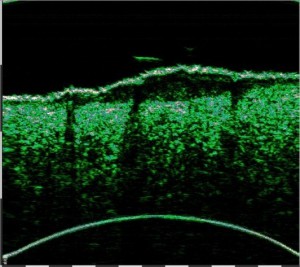

Σάρωση άθικτου δέρματος στα 75 MHz (αριστερά) και διάγραμμα της μικροανατομικής δομής του δέρματος (δεξιά).

e – επιδερμίδα, pd – θηλώδες χόριο, rd – δικτυωτό χόριο, hf – θύλακας της τρίχας, bv – αιμοφόρο αγγείο βαθέος δερματικού πλέγματος, λίπος – λιπώδης ιστός, fas – περιτονία, msc – μυς.